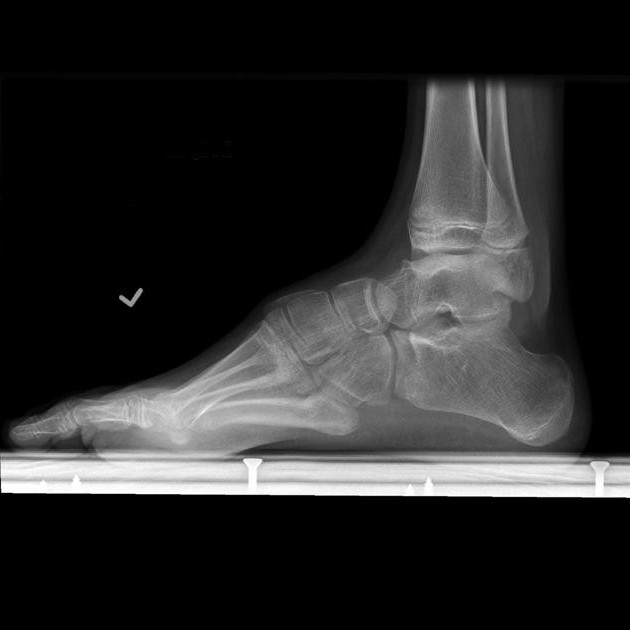

Diagnosis of flat feet includes listening to complaints, examining the external condition of the foot and probing it. The diagnosis is clarified using an x-ray. Having an x-ray, the doctor determines the type and stage of the disease. So, the question of whether they take 3 degrees to the army with flat feet is possible to answer negatively, having on their hands pictures of the feet and the conclusion of the orthopedist. There is also an easy way to determine if a recruit has a disease. This is a plant-gamma method. To do this, the sole of the foot is painted with harmless paint, after which a footprint is placed on a sheet of paper. After analyzing the trace, we can judge the presence and degree of the disease and, accordingly, determine whether they take with flat feet in the army.